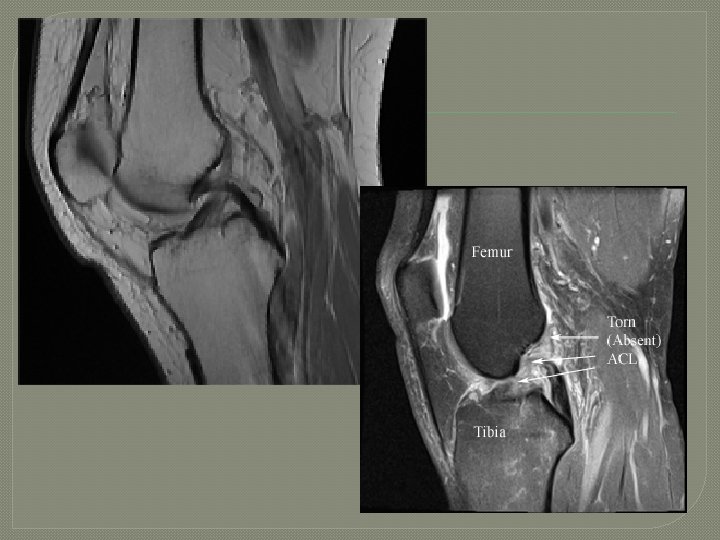

ACL Sprain Mechanism of Injury Noncontact: - decellereation - foot planted - rotation - valgus stress Contact: hyperextension w/foot planted Common Injuries Signs and Symptoms Hears or feels a “pop”, rapid swelling, joint instability. Treatment Prevention Strategies RICE, restore ROM and Lower extremity strength, surgery strengthening and required to reconstruct conditioning. the ligament.

ACL Strain cont…

Inside the Knee: ACL